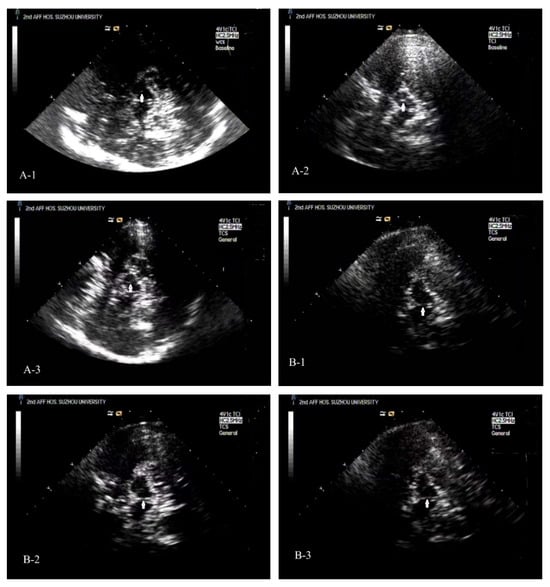

Significant differences in bilateral SN area (RSN, LSN) and SNsA were observed among the three groups (all p < 0.001; Figure 1). Post hoc analysis showed that RSN, LSN, and SNsA were significantly smaller in the ESRD + RLS group than in the ESRD − RLS and normal control groups (all p < 0.001), but no differences were found between the ESRD − RLS and control groups (all p > 0.05).

Typical TCS images of the midbrain plane of ESRD + RLS, ESRD − RLS patient, and NC [Figure 2(A-1–A-3)].

Figure 2. Typical TCS images of the midbrain plane of ESRD + RLS, ESRD − RLS patient, and NC. (A-1): A TCS image of the midbrain plane of an ESRD + RLS shows that the area of ipsilateral SN echogenicity was 0.07 cm2. (A-2): A TCS image of the midbrain plane of a normal control reveals that the area of ipsilateral SN echogenicity was 0.14 cm2. (A-3): A TCS image of the midbrain plane of an ESRD − RLS reveals that the area of ipsilateral SN echogenicity was 0.12 cm2. (B-1): A TCS image of the midbrain plane of an ESRD + RLS patient shows interrupted brainstem raphe echogenicity; (B-2): A TCS image of the brainstem raphe of a normal control exhibits continuous echogenicity. (B-3): A TCS image of the brainstem raphe of an ESRD − RLS exhibits interrupted brainstem raphe echogenicity.